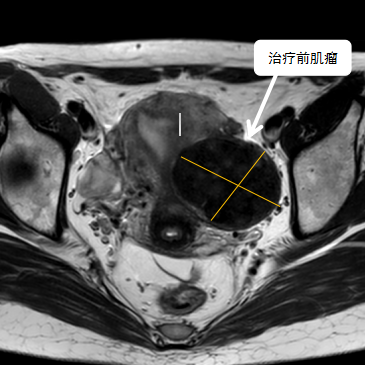

術(shù)前影像資料

經(jīng)過兩個月的藥物預(yù)處理,完善術(shù)前準備,治療當天陳主任帶領(lǐng)團隊在3.0T磁共振清晰圖像引導(dǎo)下對子宮肌瘤進行精準消融,患者全程清醒,沒有明顯疼痛,經(jīng)過1個多小時的精細操作,手術(shù)非常成功,消融率接近90%,內(nèi)膜未見損傷!觀察一個小時后患者即自行回家。

術(shù)后即刻行增強磁共振檢查,顯示病變被消融近90%,內(nèi)膜未見損傷